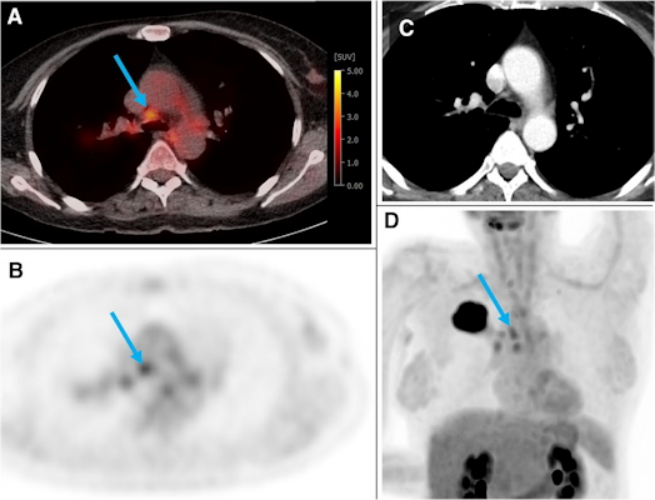

上圖來自一名訓練和測試隊列的54歲女性,患有右上葉G2腺癌(44 mm)。幾個肺門和縱隔淋巴結的F-18 FDG攝取量高于正常肝臟(PET評分為3)。藍色箭頭示N2氣管旁淋巴結,短軸7 mm,SUVmax為3.5。根據視覺評估,本例疑似N2疾病。根據梯度增強分類器模型,N2/3的概率僅為0.17。經超聲引導下同側肺門、氣管旁和隆突下LNs經支氣管穿刺活檢證實患者為N0。圖片由《歐洲核醫學和分子成像雜志》通過CC BY 4.0提供。